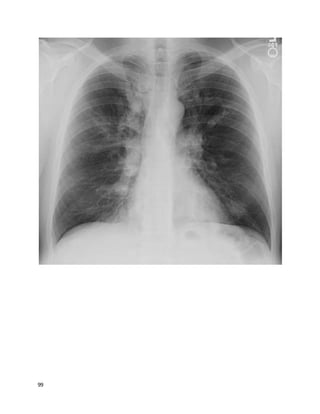

You receive an email from a colleague asking for a "curbsideconsult." You haven't

heard the story or your colleague's question yet, but to frame your thinking, you

quickly glance at the images she's attached to the email.

The chest X-ray shows reticulonodular opacities, a nonspecific abnormal finding.

The axial CT cuts show:

 Small nodules in a lymphangitic pattern, i.e., touching the pleura/fissures

 Pleural effusions with an irregular, nodular contour

9

 Irregular thickening of the interlobular septa

 Peribronchovascular thickening

All these findings are consistent with this patient's diagnosis of lymphangitic

carcinomatosis(LC): diffuse metastatic spread of cancer to the lungs, where it

diffusely infiltrates and obstructs lymphatic channels. 80% of cases are due to

adenocarcinomas, most often from a primary cancer of the breast, lung, or colon.

This case of LC was from a primary pancreatic adenocarcinoma.

Chest films are usually normal in lymphangitic carcinomatosis.